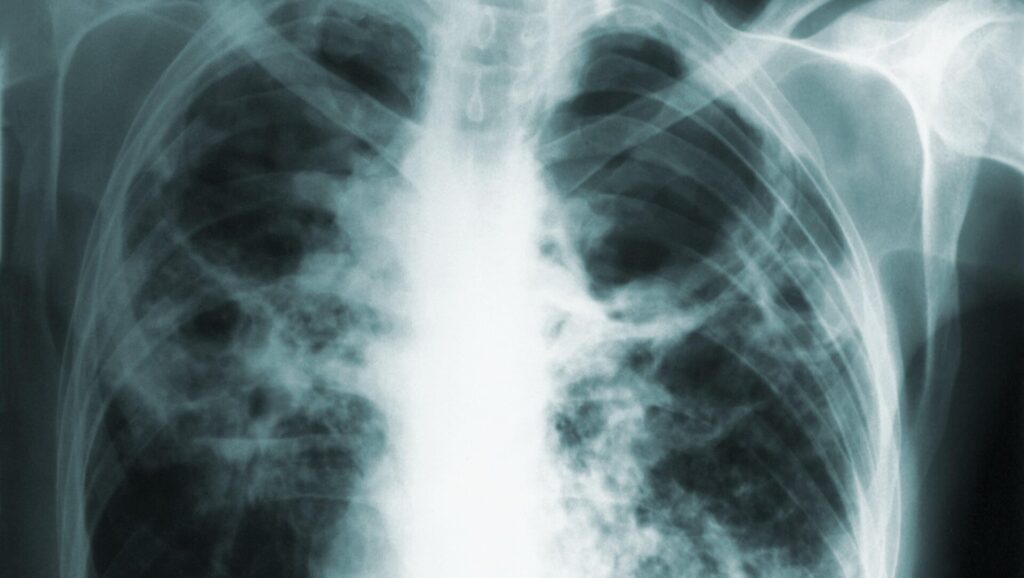

For more than a year, a woman reportedly refused to obey court orders to stay at home and exposed others to her active TB infection.